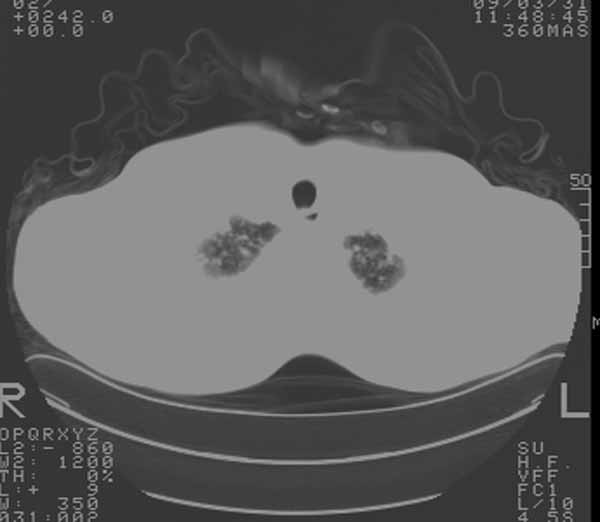

以下是引用余辉在2009-3-31 18:43:00的发言:[br]肺水肿,双侧心腔积液,心包积液,心影增大,疑似心衰

以下是引用wangyong1977在2009-3-31 20:46:00的发言:[br]肺水肿,双侧胸腔积液,心包积液,心影增大,疑似心衰 [br]

以下是引用宇宙ct在2009-3-31 18:57:00的发言:[br]肺水肿,双侧心腔积液,心包积液,心影增大,疑似心衰 [br] [br]